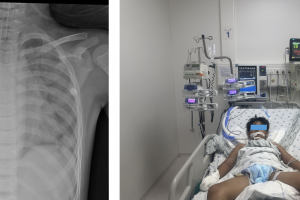

Cứu sống một trẻ viêm cơ tim tối cấp, sốc tim, rối loạn nhịp tim nặng – Vừa qua, Bệnh viện Nhi Đồng Thành Phố tiếp nhận trẻ V. T. N. Tr. 7 tuổi, nữ, ngụ...